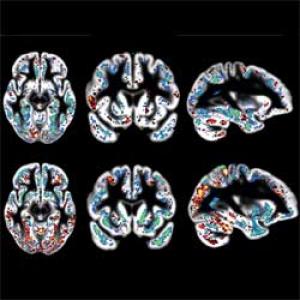

Σικάγο: Απεικονιστικές εξετάσεις ενδεχομένως να είναι ικανές να ανιχνεύσουν τα πρώιμα σημάδια της νόσου Αλτσχάιμερ πολύ πριν αρχίσει να επηρεάζει την μνήμη, γεγονός που μπορεί να συντελέσει σε πρώιμη διάγνωση και πιο αποτελεσματικά θεραπευτικά σχήματα.